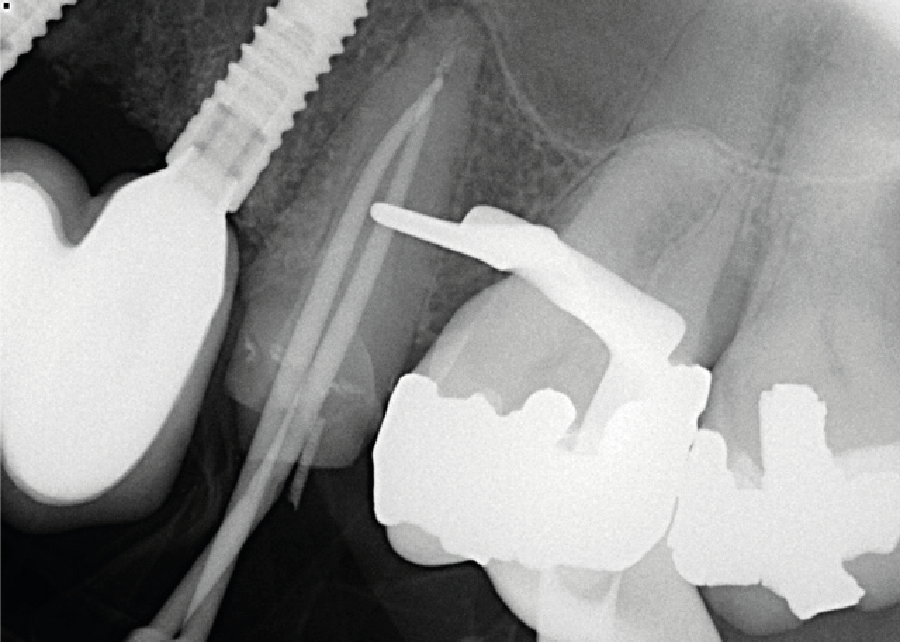

Cone fit radiograph

• A second appointment was scheduled, and thorough chemo-mechanical preparation was completed with Protaper Gold nickel titanium files and finished to 30/.09. The two separate canals merged at 16mm to a single canal in the apical 3.5mm. Obturation was completed with taper matched gutta-percha cones, warm vertical compaction, and AH plus sealer.